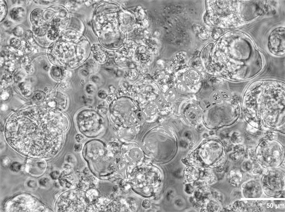

2. 突破胶原凝胶培养瓶颈,实现临床级材料适配

胶原 I 是临床常用的 ECM 材料(已用于组织修复),但单独使用时类器官生长效率极低。scTS2/16 通过激活 α2β1 整合素(胶原 I 受体),增强胶原黏附与生长:结肠类器官单细胞在胶原 I 上的黏附量,在 scTS2/16 作用下从 7.5×10⁵ RLU 提升至 22.5×10⁵ RLU。CRISPR 敲除 α2 整合素(ITGA2⁻/⁻)后,类器官无法在胶原中生长,证实 α2β1 整合素是关键。支持原代类器官培养:新鲜结肠活检组织在胶原 I+scTS2/16 中,类器官产量从平均 6 个 / 孔提升至 25 个 孔。胆管原代类器官产量提升 2 倍。

scTS2/16改善了PureCol EZ Gel中原发性细胞器的整合素α2β1介导的生长(Wim B et al., 2025)